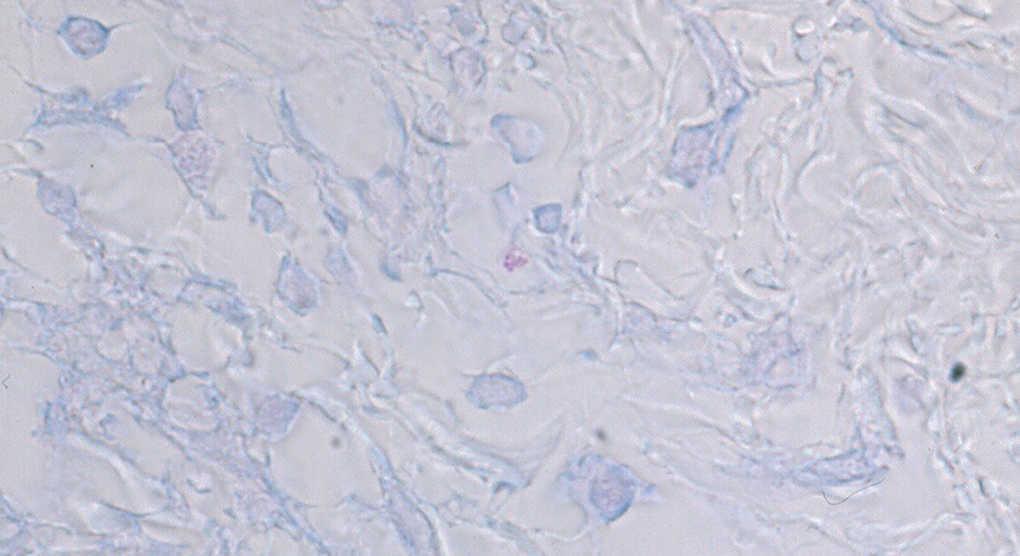

Se practicó biopsia de una de las placas observándose un denso infiltrado inflamatorio compuesto en su mayoría por linfocitos e histiocitos, rodeando vasos y nervios, con lesión neurológica incipiente. El infiltrado ocupaba toda la dermis y se extendía hasta el tejido celular subcutáneo. Se observaba una clara banda subepidérmica respetada, que separaba epidermis de dermis. La tinción de Ziehl-Nielsen demostró bacilos ácido-alcohol resistentes (BAAR) (fig. 2).

Fig. 2.--Tinción de Ziehl-Nielsen que demuestra varios bacilos ácido-alcohol resistentes en el interior de macrófagos. (Ziehl-Nielsen, x100.)